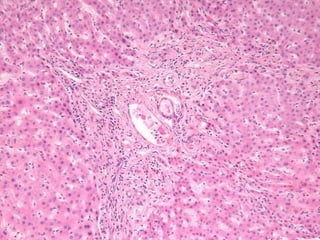

1206/82 54 yo women with Ulcerative Colitis.

LS 1206/82  Dx: Bile duct injury and paucity compatible with primary sclerosing cholangitis Comment: There is focal, marked portal expansion by ductular reactions, inflammatory infiltrates and fibrosis.

1206/82 54 yowomen with Ulcerative Colitis.